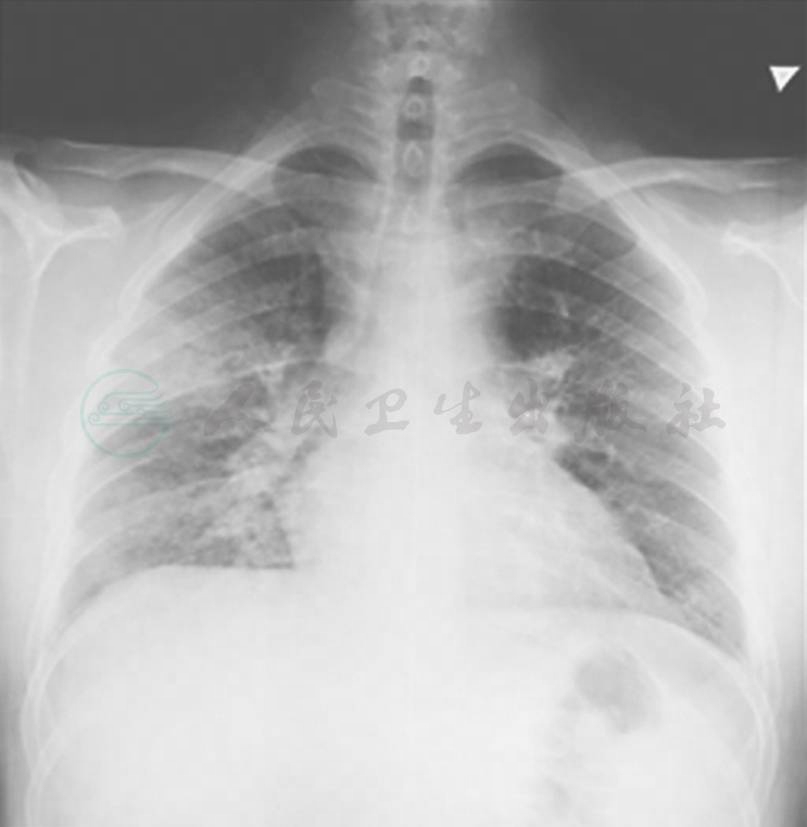

【影像学检查】

胸部CT:双侧多发高密度阴影,右肺可见明显腺泡征(图2)。

图2 胸部CT表现

但是,在肺部感染影像学改变中,大叶性肺炎典型表现为实变、大片高密度阴影,在肺叶、肺段分布,其中可见支气管充气征;小叶性肺炎典型表现为斑片状阴影,外周密度较浅,边缘模糊;间质性肺炎典型表现为不规则条索、网状、点状影。而本例患者胸部CT表现为双侧肺可见高密度阴影,右下肺可见密集腺泡征,似梅花花瓣,在肺部感染影像学表现中实属罕见。